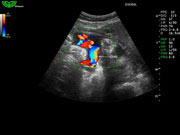

Система поддерживает СFM-режим, PW-режим, CW-режим, режим направленного энергетического потока, режим Color-M, панорамный режим, ECG, DICOM 3.0 и универсальные пакеты программ для кардиологии, сосудистого исследования и акушерства.

Режимы изображения: B, 2B, B/M, B/BC, CFM, PW, HPRF, PD, направленный PD, CW, режим Color M.

Дополнительные возможности: триплекс, трапециидальное отображение, анатомический М-режим, «free-hand» трехмерная реконструкция, авто-доплер.